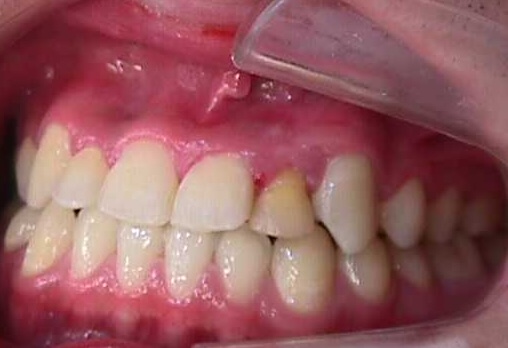

【矯正症例】左上2番3番逆転症例2

Before

After

左上2番3番逆転症例

随分、前の症例で現在、写真しか残っておりません。

治療費や、治療期間を掲載できないことをご了承ください。

私の矯正歯科医の人生の中でも、特に思い出深い症例です。